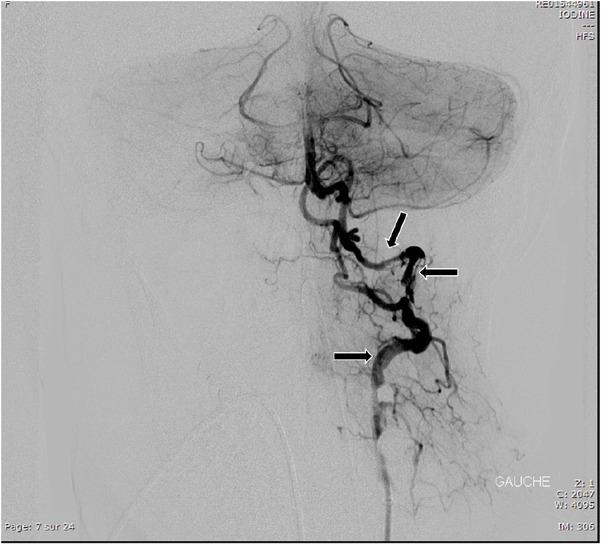

A 34-year-old woman was manipulated on the cervical spinal column by a chiropractor. Following three weeks of cervical pain, she presented with severe aphasia and quadriplegia (NIHSS = 28). An MRI scan indicated ischemia of the vertebrobasilar system. Thirty-one hours after the onset of these symptoms, a thrombectomy was performed. After one month, the patient could move her head and the proximal part of her limbs but remained confined to bed (NIHSS = 13).

一名34岁女性接受了脊椎按摩师的颈椎推拿。在颈部疼痛三周后,她出现了严重失语和四肢瘫痪(美国国立卫生研究院卒中量表评分=28)。磁共振成像扫描显示椎基底动脉系统缺血。这些症状出现31小时后进行了血栓切除术。一个月后,患者能够移动头部和四肢近端,但仍需卧床(美国国立卫生研究院卒中量表评分=13)。